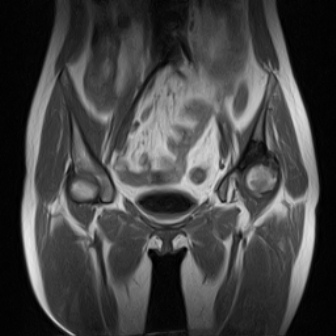

请看看我的片子,我得的什么病,该怎么治疗?谢谢[img][/img]

片子不全,应该是左侧股骨头无菌坏死,右侧似乎没问题,到正规医院治疗,千万别看广告去小医院,吃中药什么的,都是骗人的(说了也白说,百分百都得让人骗点钱才甘心。)

应该是左侧股骨头无菌坏死